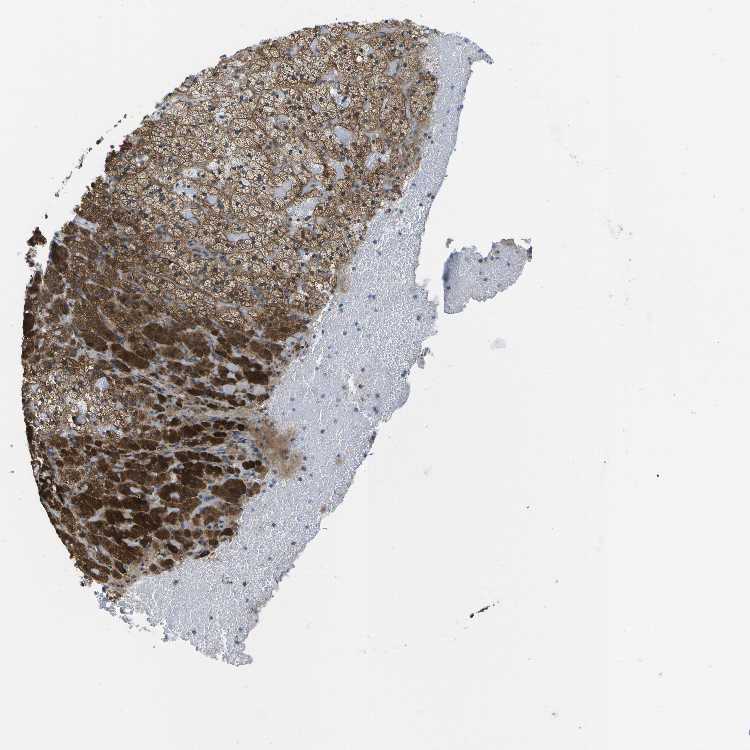

ADRENAL GLAND - Antibody stainingi

Antibody staining in the annotated cell types in the current human tissue is reported as not detected, low, medium, or high, based on conventional immunohistochemistry profiling in selected tissues. This score is based on the combination of the staining intensity and fraction of stained cells.

Each image is clickable and will lead to virtual microscopy that enables deeper exploration of all samples and also displays staining intensity scores, fraction scores and subcellular localization as well as patient and tissue information for each sample.

Antibody HPA016961

Glandular cells High